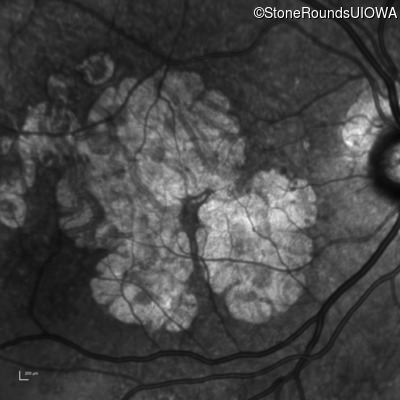

AR Stargardt Disease (IIA)

Age at visit: 59 years

This 59 year old man has noticed some blank spots near the center of his vision over the last 2 years.

Diagnosis & molecular findings

Disease Gene Allele 1 variant(s) Allele 2 variant(s) Inheritance mode

AR Stargardt Disease ABCA4 Leu2027Phe CTC>TTC IVS30+1321 A>G AR